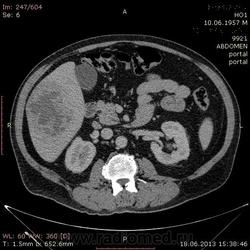

На абсцесс похоже

+1. Контраст вводили?

На мой взгляд, абсцесс.

Тоже за абсцесс.

Cпасибо , коллеги.Сегодня больного прооперировали диагноз абсцесс правой доли печени.Оказывается больной когда - то получил тупую травму живота, об этом нам не говорил.....